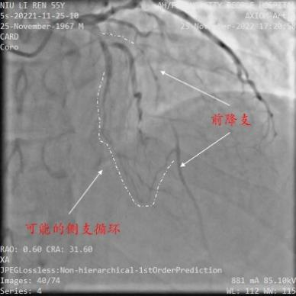

2月中旬,某患者,牛XX,男性,55岁,因冠心病、不稳定型心绞痛入住安徽省阜阳市人民医院,选择性冠状动脉造影(coronary angiography,CAG)示前降支7段和回旋支13段为CTO,右冠脉2段为重度狭窄,病变复杂,病情危重(图1)。当地医院反复尝试,历时约2小时前降支和回旋支均未能开通,遂建议患者3月后再次尝试PCI或选择CABG治疗。患者2月后慕名去武汉亚洲心脏病医院接受介入治疗,但尝试约2小时仍然未能开通前降支CTO(图2),建议患者接受CABG治疗。

图1 安徽省阜阳市人民医院手术资料